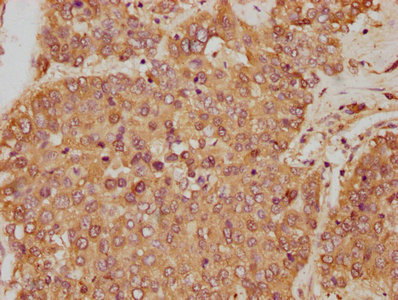

IHC image of CSB-PA009679HA01HU diluted at 1:250 and staining in paraffin-embedded human liver cancer performed on a Leica BondTM system. After dewaxing and hydration, antigen retrieval was mediated by high pressure in a citrate buffer (pH 6.0). Section was blocked with 10% normal goat serum 30min at RT. Then primary antibody (1% BSA) was incubated at 4°C overnight. The primary is detected by a biotinylated secondary antibody and visualized using an HRP conjugated SP system.